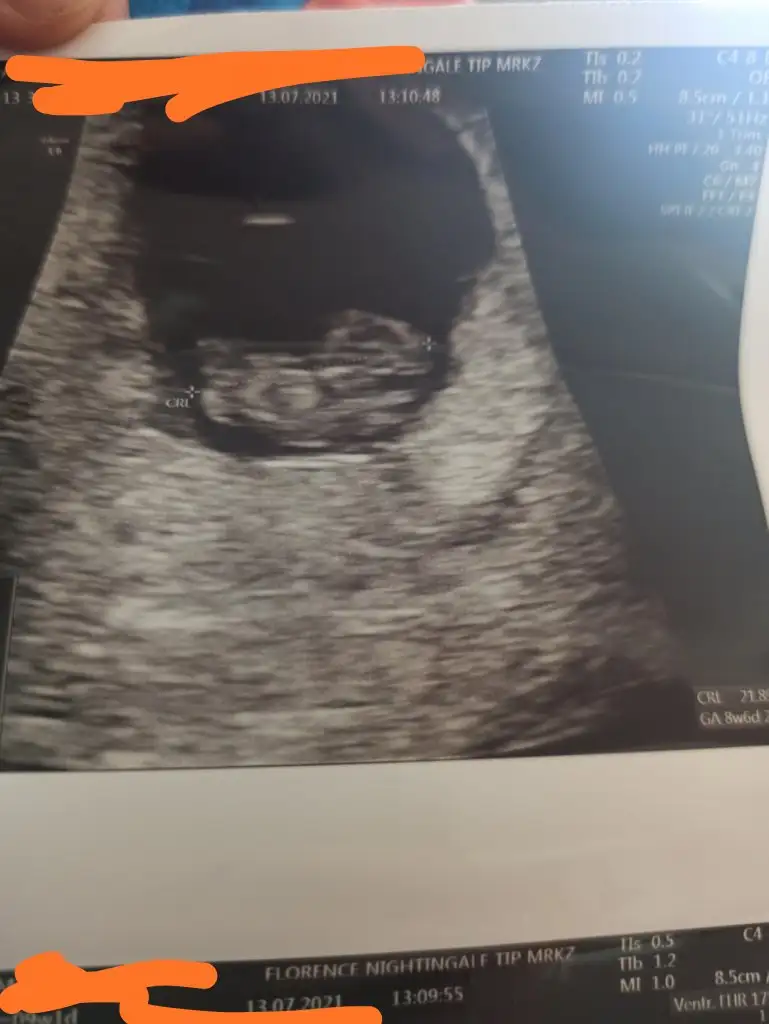

Erkek gibimerhaba :) ben de ekledim fotoğrafları. ilki 5 hafta, ikincisi 9 hafta. her ikisi de karından

Böyle bir bilgi bulmuştum bugünmerhaba :) ben de ekledim fotoğrafları. ilki 5 hafta, ikincisi 9 hafta. her ikisi de karından

O haftalarda vajinal bakilanlara da baktim, erkege uyuyorBöyle bir bilgi bulmuştum bugün![]()